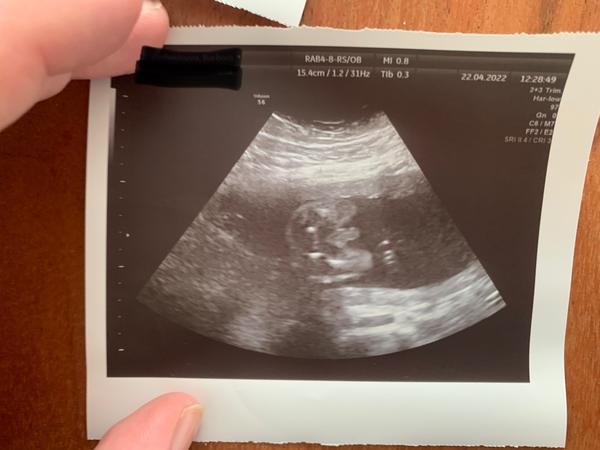

Ahojte baby ja som len nedockava a viem že to nieje vidno ale zaujímalo by ma či sa da aj podľa hlavičky alebo nejakého iného faktu rozpoznať čo by fo mohlo byt toto je 12+5 len malo stále spojené nôžky 🙂

@rebeka3333 pohlavny hrbolcek nevidno...ak je ten rovnobezne s chrbticou tak by malo byt dievca a ak zviera urcity uhol tak chlapcek

Podla skull teorie asi skor chlapcek, medzi nozicky ako pises nevidno...takze stale to mas 50/50